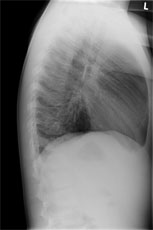

Zur Aufnahme kommt ein 8 jähriger Knabe mit hartnäckigem, vorwiegend trockenem Reizhusten seit 5 Tagen und subfebrilen Temperaturen bis mässigem Fieber.

Bei relativ blander Klinik wird ein Thoraxröntgen durchgeführt: